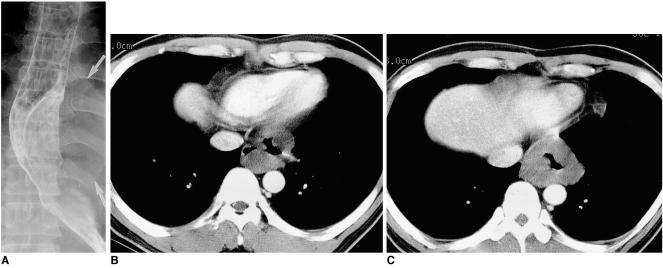

The tumors, surgical specimens of which ranged from 9 to 90 mm in diameter, were located in the upper (n = 1), middle (n = 5), or lower esophagus (n = 6). In ten of the 12 patients, chest radiography revealed the tumors as mediastinal masses. Esophagography showed them as eccentric, smoothly elevated filling defects in 11 patients and a multilobulated encircling filling defect in one. In 11 of the 12 patients, enhanced CT scans revealed a smooth (n = 9) or lobulated (n = 2) tumor margin, and attenuation was homogeneously low (n = 7) or iso (n = 4). In one patient, the tumor signal seen on T2-weighted MR images was slightly high.

Esophageal leiomyomas, located mainly in the middle or distal esophagus, are consistently shown by esophagography to be mainly eccentrically elevated filling defects and at CT, lesions showing homogeneous low or isoattenuation are demonstrated.